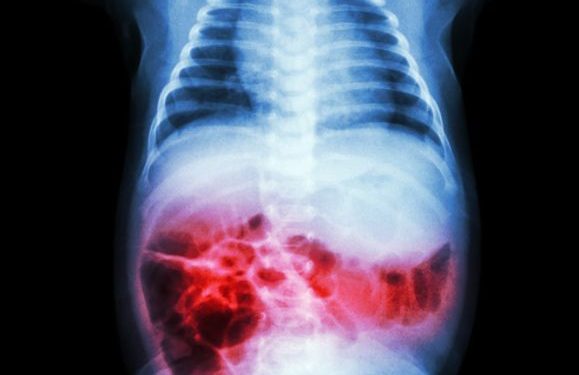

When your doctor suspects NEC, they will order a series of medical tests that will help them determine the cause and severity of the disease. These include a blood test to check for bacteria, a fecal test to check for evidence of blood in your baby’s poop, and an abdominal X-ray to see if air bubbles (called pneumatosis intestinalis) are present within your child’s intestine.

These X-rays may show multiple small bubbles in the intestine (pneumatosis intestinalis) or free air in the large veins that carry blood to the lungs (portal venous air). This can indicate a damaged intestine, a perforation, or a hole in your child’s bowel.